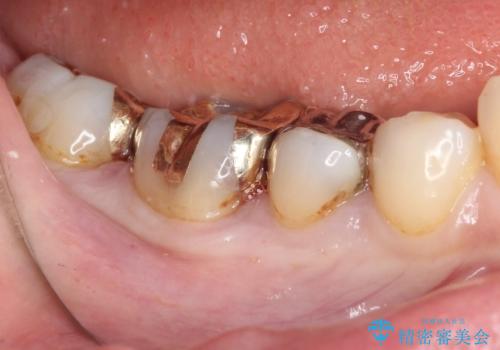

下の奥歯の虫歯をゴールドインレーで治療

精度が高く、虫歯の再発リスクの低いゴールドインレーで治療を行うこととしました。

ゴールドインレーは適合がよいため、虫歯の再発のリスクが少ない非常に優れた材料です。

ゴールドインレーはセラミックインレーと比べ、割れるリスクが低いため、咬合力が強い方にお勧めです。